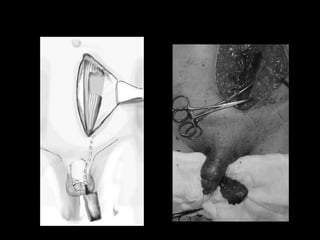

Diagnostico

•    Palpacion de hematoma

•    Incurvarcion

•    Uretrografia retrograda

•    Cavernosografia

•    USG Doppler

•    RMN

Tratamiento

• Contusiones leves

Antibiotico, Antinflamatorios y frio local

• Contusion con hematoma

Colocacion de sonda (tipo Foley 14-16F)

Drenaje de hematoma